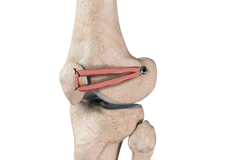

Ligaments of the Knee

Ligaments are tough bands of tissue that connect one bone to another bone. The ligaments of the knee stabilize the knee joint. There are two important groups of ligaments that hold the bones of the knee joint together, collateral and cruciate ligaments.

Collateral ligaments are present on either side of the knee. They prevent the knee from moving too far during side to side motion. The collateral ligament on the inside is called the medial collateral ligament (MCL) and the collateral ligament on the outside is called the lateral collateral ligament (LCL).

Cruciate ligaments, present inside the knee joint, control the back-and-forth motion of the knee. The cruciate ligament in the front of the knee is called anterior cruciate ligament (ACL) and the cruciate ligament in the back of the knee is called posterior cruciate ligament (PCL).